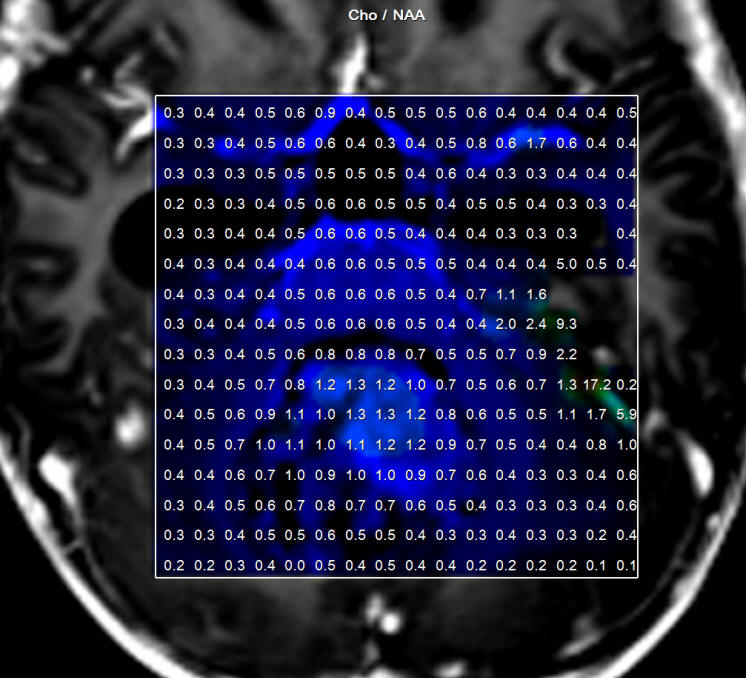

Below, showing a case with posterior third ventricular anaplastic ganglioma in 30 years old patient to whom intraoperative MRI with spectroscopy, SWI and MRA were performed twice to confirm the total resection of the tumor. See fig-1-7.

Fig-1: Choline distribution showing a small nidus of possible malignant character befor attacking the lesion.

Fig-5: Choline elevation confirming still persisting active sites intermingled with the hematoma in the right side.

Fig-32: Choline distribution in the medulloblastoma.

Fig-33: Cho/NAA ration distribution of the medulloblastoma.